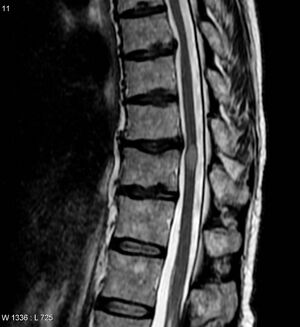

MRI image of transverse myelitis patient's spinal cord | |